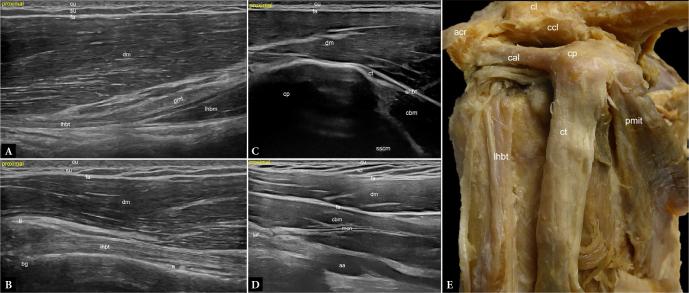

推进高分辨率肌肉骨骼超声:一种基于组织学和解剖学的方法以增强肩部成像。第2部分:肩部前侧和外侧

Advancing high-resolution musculoskeletal ultrasound: a histology- and anatomy-driven approach for enhanced shoulder imaging. Part 2: Anterior and lateral shoulder.

Ultrasonography is a reliable imaging technique for the accurate diagnosis and evaluation of musculoskeletal disorders. Recent developments in ultrasound technology have significantly increased image resolution, making it possible to see anatomical features at almost microscopic dimensions. Current standards for standardized shoulder ultrasonography mostly depend on outdated machine types and configurations that may not fully utilize these high-resolution imaging capabilities. In this article, we give a clear and comprehensive introduction to high-resolution shoulder sonography, using histological and anatomical images from cadavers for comparison. Images collected using contemporary technology are shown, and international standard practices are considered. The examination and normal results are presented in a methodical manner, beginning posteriorly, moving frontally, then more anteriorly, and concluding with a lateral and optional axillary examination. This article focuses on the anterior and lateral shoulder.

摘要

超声检查是一种用于准确诊断和评估肌肉骨骼疾病的可靠成像技术。超声技术的最新发展显著提高了图像分辨率,使得几乎能够以微观尺寸观察解剖特征。目前标准化肩部超声检查的标准大多依赖于过时的机器类型和配置,这些可能无法充分利用这些高分辨率成像能力。在本文中,我们使用来自尸体的组织学和解剖图像进行比较,对高分辨率肩部超声检查进行清晰而全面的介绍。展示了使用当代技术收集的图像,并考虑了国际标准做法。检查和正常结果按有条不紊的方式呈现,从后部开始,向前移动,然后更靠前,最后进行外侧和可选的腋窝检查。本文重点关注肩部的前部和外侧。